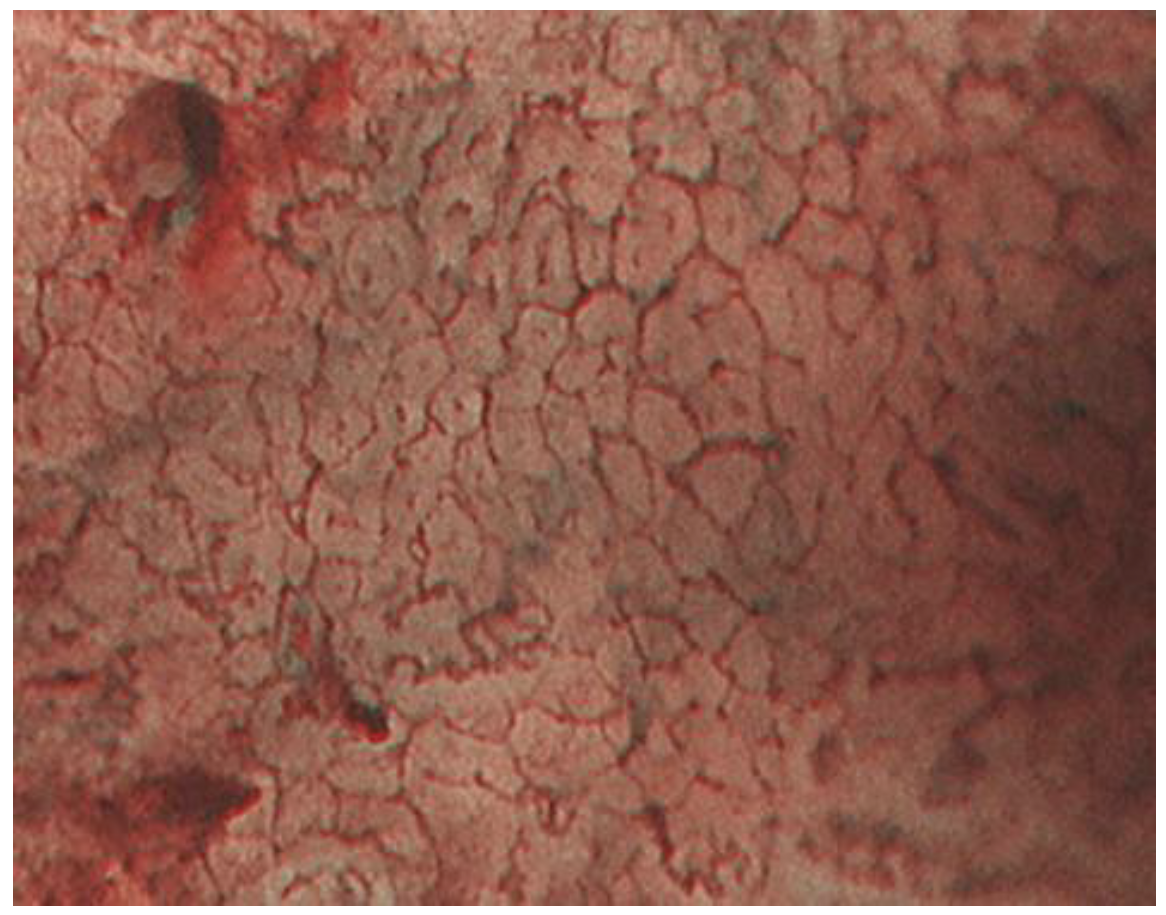

2.1. ME-NBI for Gastric Non-Cancerous Mucosa

| Micro surface pattern | morphology: homogeneous (uniform linear, curved, oval, circular) distribution: symmetric arrangement: regular | morphology: heterogeneous (irregular linear, curved, oval, circular) distribution: asymmetric arrangement: irregular |

| Micro vascular pattern | morphology: uniform distribution: symmetric arrangement: regular | morphology: heterogeneous (dilatation, heterogeneity in shape, abrupt caliber alteration, tortuousness) distribution: asymmetric arrangement: irregular |